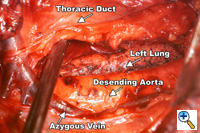

Figure 1. View from a right thoracotomy. Specimen is mobilized anteriorly along the descending thoracic aorta including the thoracic duct. Figure 1. View from a right thoracotomy. Specimen is mobilized anteriorly along the descending thoracic aorta including the thoracic duct. |

A right fifth interspace thoracotomy is performed regardless of the location of the tumor within the esophagus. The "first field" comprises the middle and lower mediastinum and is bounded superiorly by the tracheal bifurcation, inferiorly by the esophageal hiatus, anteriorly by the hilum of the lung and pericardium and posteriorly by the descending thoracic aorta and the spine. The en-bloc resection of the middle and lower mediastinum begins by incising the mediastinal pleura over the anterior aspect of the azygous vein from the level of the azygous arch superiorly to the aortic hiatus inferiorly. The dissection proceeds leftwards anterior to the aorta and across the mediastinum to the opposite pleura, which is entered along the entire length of the incision. The thoracic duct is thus mobilized anteriorly towards the specimen and is ligated inferiorly at the aortic hiatus and superiorly as it crosses to the left side of the mediastinum (Figure 1). The arch of the azygous vein, but not its main trunk, is resected en-bloc with the specimen. The anterior dissection is commenced by division of the azygous vein at its caval junction and by carrying the dissection along the right main bronchus and the posterior aspect of the hilum of the right lung. The hilar and subcarinal nodes are cleared and a patch of pericardium is resected en-bloc with the tumor-bearing esophagus if the latter abuts the pericardial sac.